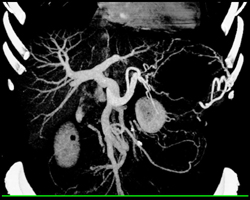

Hepatoblastoma